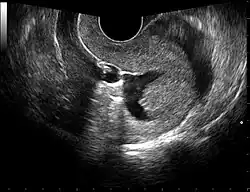

Gynecologic ultrasonography or gynecologic sonography refers to the application of medical ultrasonography to the female pelvic organs (specifically the uterus, the ovaries, and the fallopian tubes) as well as the bladder, the adnexa, and the recto-uterine pouch. The procedure may lead to other medically relevant findings in the pelvis.This technique is useful to detect myomas or mullerian malformations.

The examination can be performed by transabdominal ultrasonography, generally with a full bladder which acts as an acoustic window to achieve better visualization of pelvis organs, or by transvaginal ultrasonography with a specifically designed vaginal transducer. Transvaginal imaging utilizes a higher frequency imaging, which gives better resolution of the ovaries, uterus and endometrium (the fallopian tubes are generally not seen unless distended), but is limited to depth of image penetration, whereas larger lesions reaching into the abdomen are better seen transabdominally. Having a full bladder for the transabdominal portion of the exam is helpful because sound travels through fluid with less attenuation to better visualize the uterus and ovaries which lies posteriorly to the bladder. The procedure is by definition invasive when performed transvaginally. Scans are performed by health care professionals called sonographers, or gynecologists trained in ultrasound.

Through transvaginal sonography ovarian cysts can be aspirated. This technique is also used in transvaginal oocyte retrieval to obtain human eggs (oocytes) through sonographic directed transvaginal puncture of ovarian follicles in IVF.